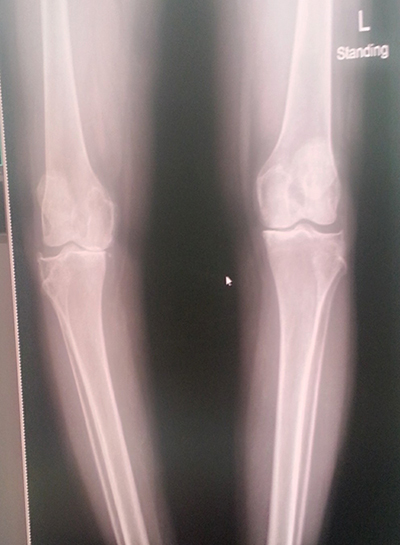

พอไปถึงก็จับเอ็กซ์เรย์ เพื่อรอแผ่นฟิล์มให้คุณหมอตรวจดู อาการเข่าเสื่อมของแม่ ก็พบว่าข้างขวาเสื่อมแน่ ๆ ส่วนข้างซ้าย ก็มีอาการเสื่อมแต่น้อยกว่า ตัดสินใจผ่าทีเดียวทั้งสองข้าง การผ่าตัดมีทั้งเปลี่ยนเฉพาะบางส่วน และเปลี่ยนเต็มข้อ สำหรับของแม่จัดเต็มข้อทั้งสองข้างเลยทีเดียว

ฟิล์มเอ็กซเรย์ก่อน (ภาพซ้าย) และหลัง (ภาพขวา) ของการผ่าตัดข้อเข่าเทียม ส่วนก้อนสีขาว ๆ ของภาพทางขวามือ คือข้อเข่าเทียมที่ใส่เข้าไป